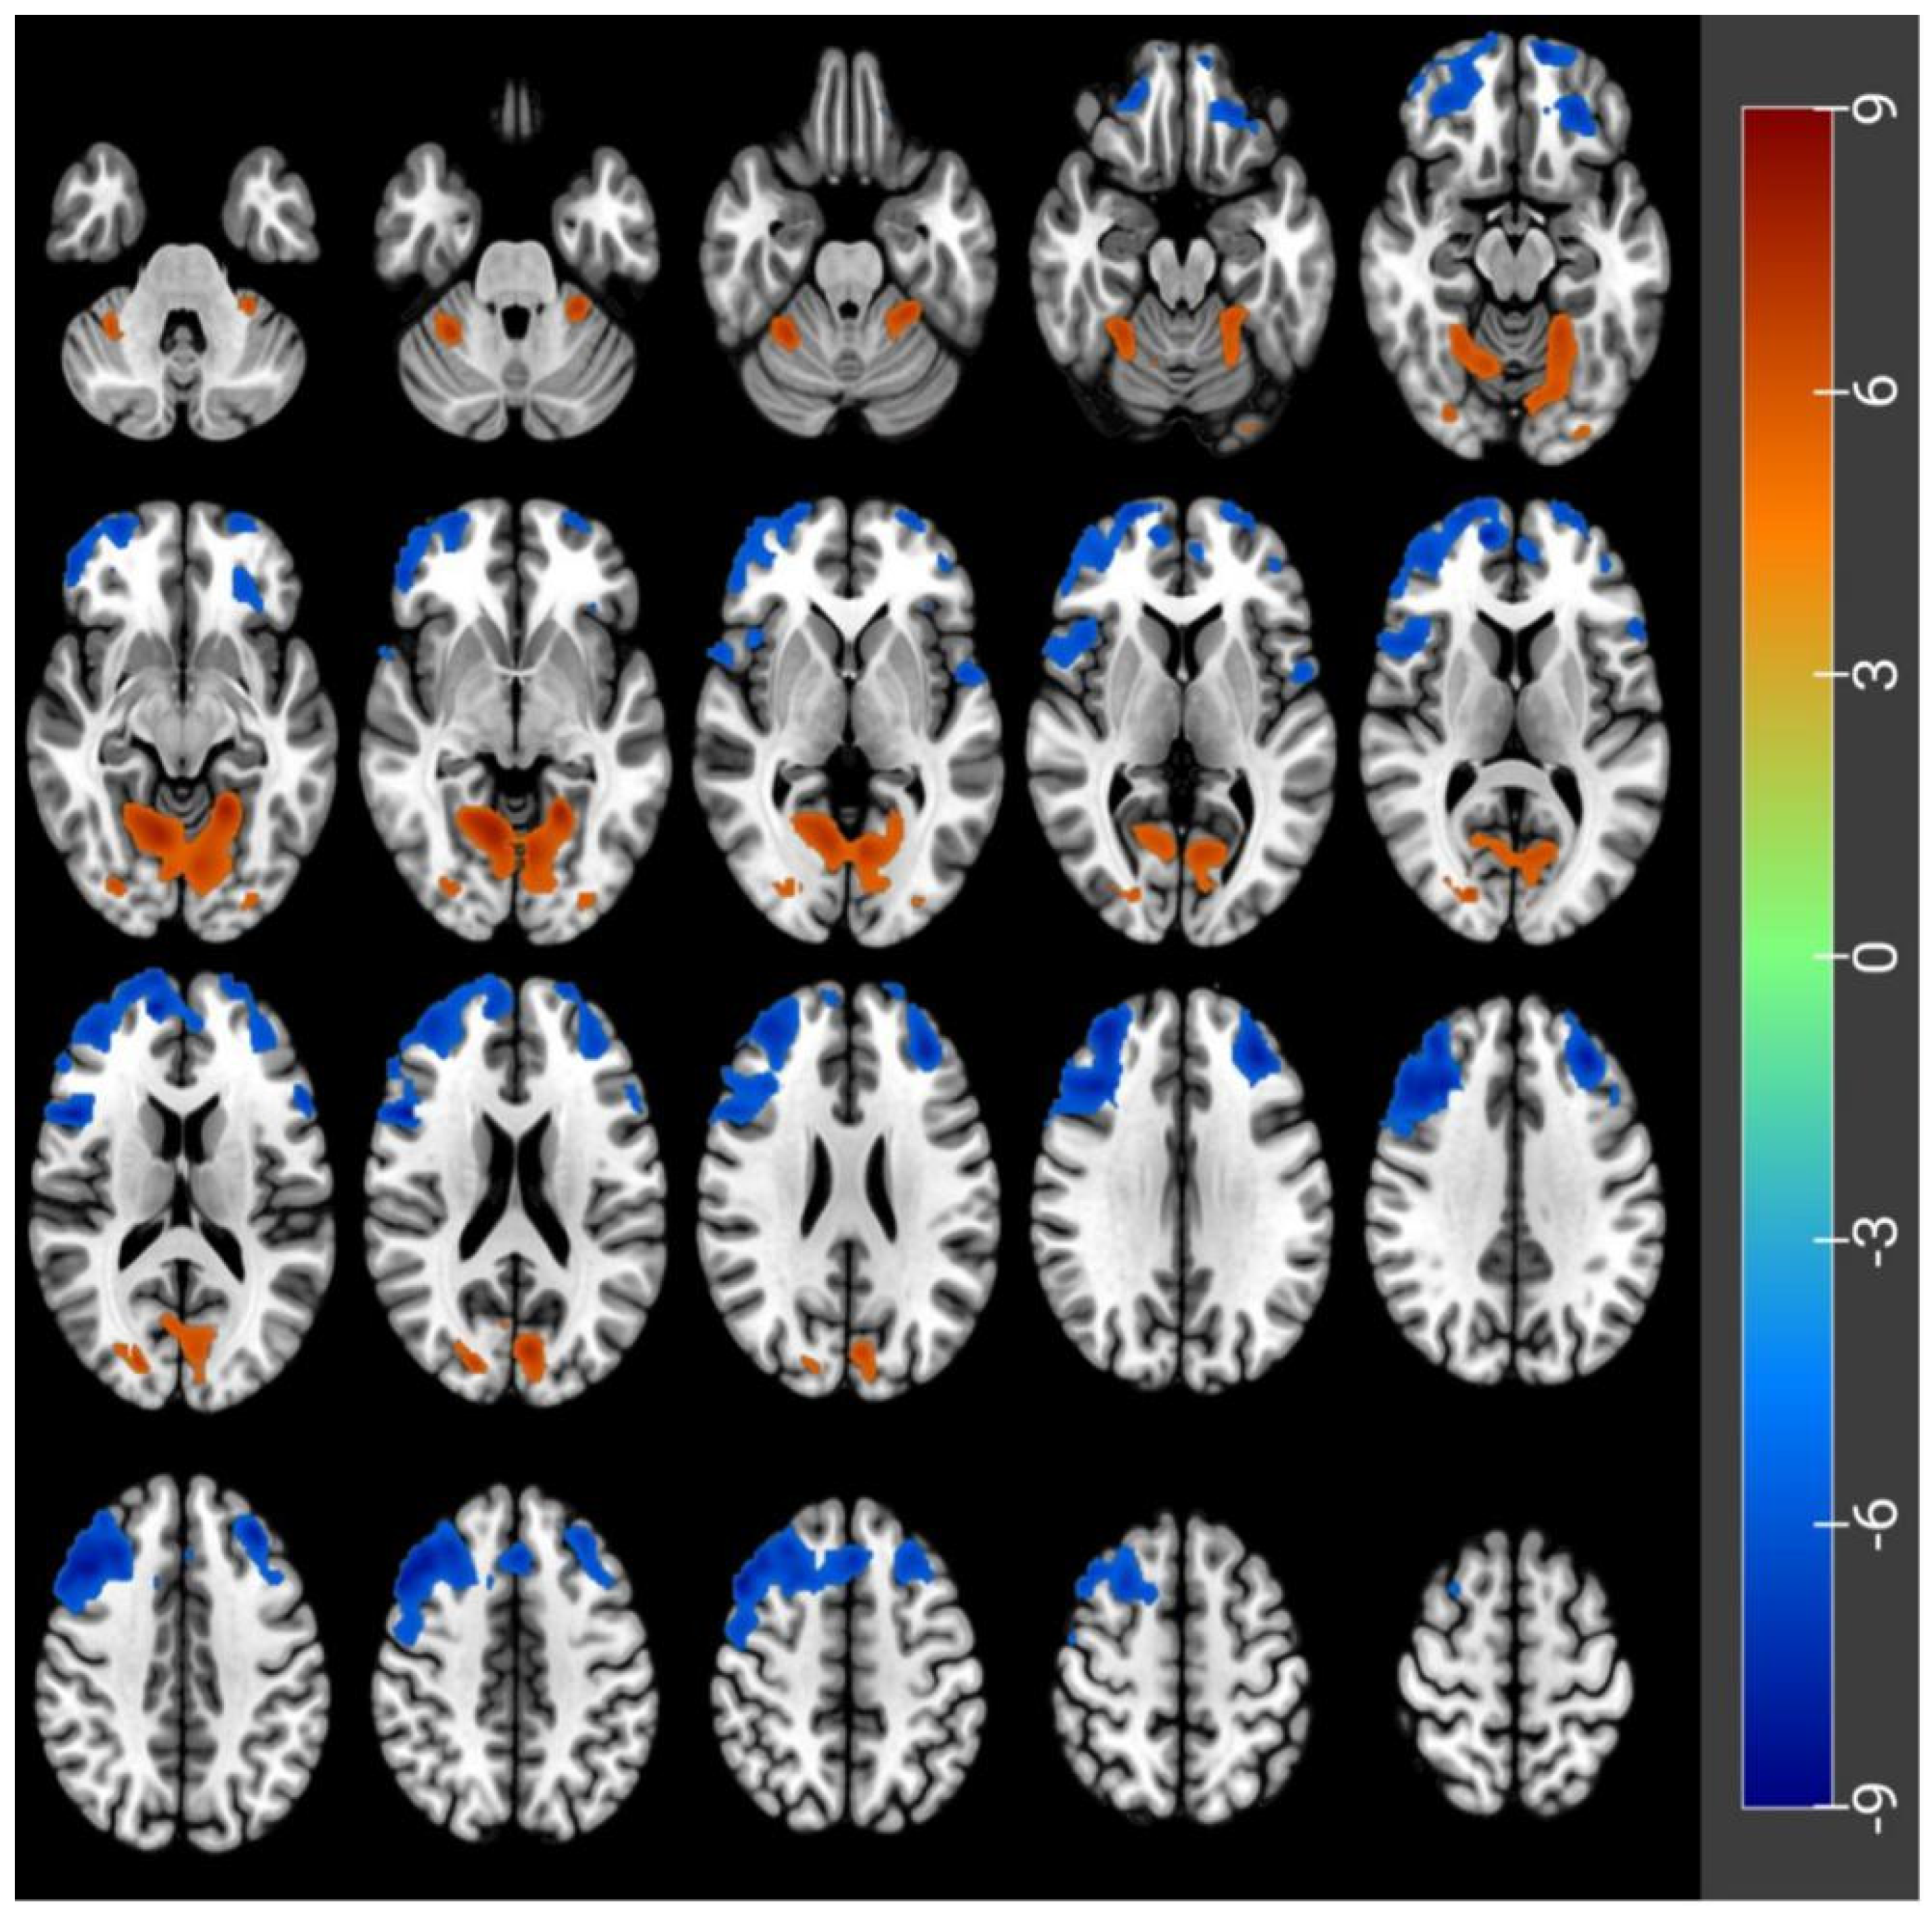

3.2. CBF Differences before and after Acute SD

| Peak Location | Side | Cluster Size | MNI Coordinates | Peak t-Score | p-Value Correctedby FWE | ||

|---|---|---|---|---|---|---|---|

| X | Y | Z | |||||

| Frontal_Mid_Orb | L | 372 | −26 | 40 | −18 | −7.2 | <0.05 |

| Frontal_Sup_Orb | L | 2006 | −12 | 62 | −18 | −9 | <0.05 |

| Frontal_Inf_Oper | R | 7735 | 48 | 14 | 18 | −8.56 | <0.05 |

| Frontal_Inf_Tri | L | 121 | −56 | 22 | 14 | −7.19 | <0.05 |

| Rolandic_Oper | L | 116 | −54 | 2 | 2 | −7.07 | <0.05 |

| Lingual | L | 3910 | −20 | −52 | −8 | 8.29 | <0.05 |

| Occipital_Sup | R | 346 | 20 | −84 | 18 | 7.06 | <0.05 |